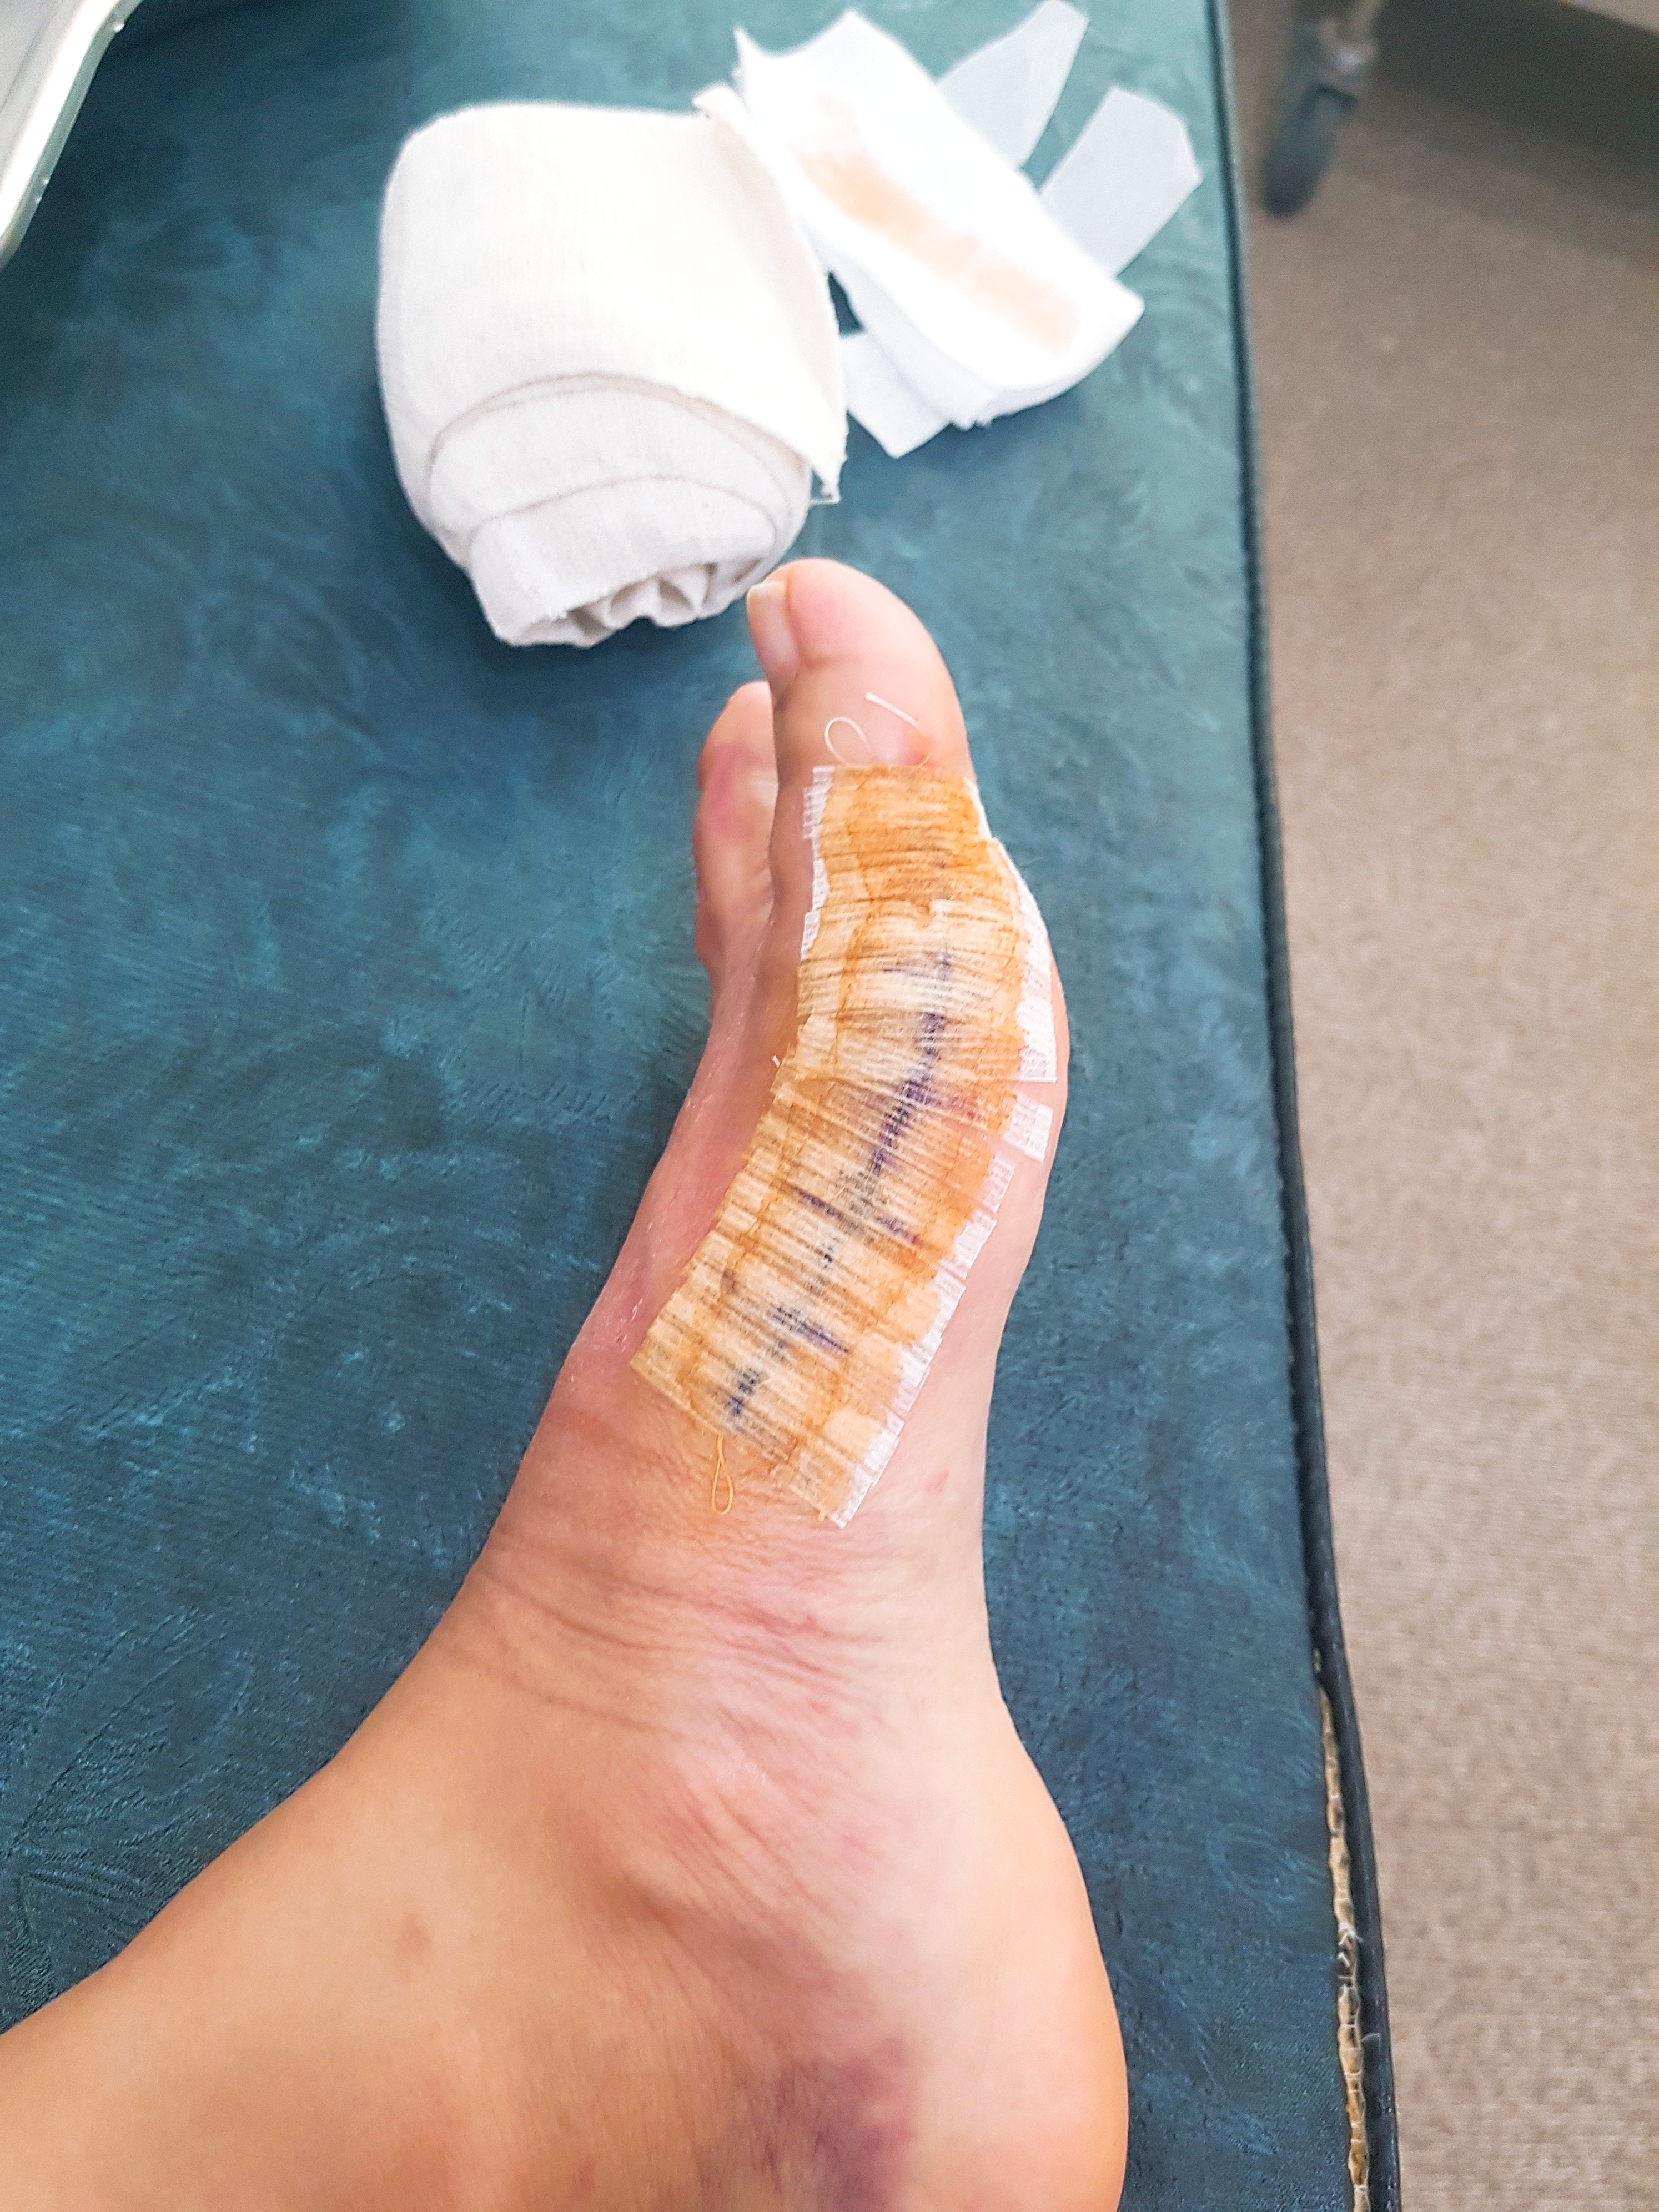

요사진은 10일정도 된 덜 험한 아기 코끼리 발사진이에요 ㅋㅋ

실밥을 드디어 떼러갔던 모습인데요.

사실 제인쨘은 이게 제일 아팠어요. 따끔따끔 😢